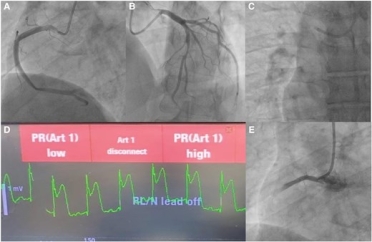

Silent stenosis to sudden shock: the unplanned culprit

What are the next best steps in the management of this patient?

1. IV heparin, dual antiplatelet therapy, glycoprotein IIb/IIIa inhibitors, consideration of thrombectomy.

2. Vasopressor support, urgent transthoracic echocardiography, preparation for mechanical circulatory support—request cardiothoracic surgeon backup.

3. Intracoronary nitroglycerin, serial ECG monitoring, repeat angiographic views, possible PCI.

4. Supplemental 100% oxygen, guidewire insertion, catheter aspiration through guiding/microcatheter, intracoronary saline/contrast flushes, intracoronary vasodilators (e.g. adenosine, nitroprusside).